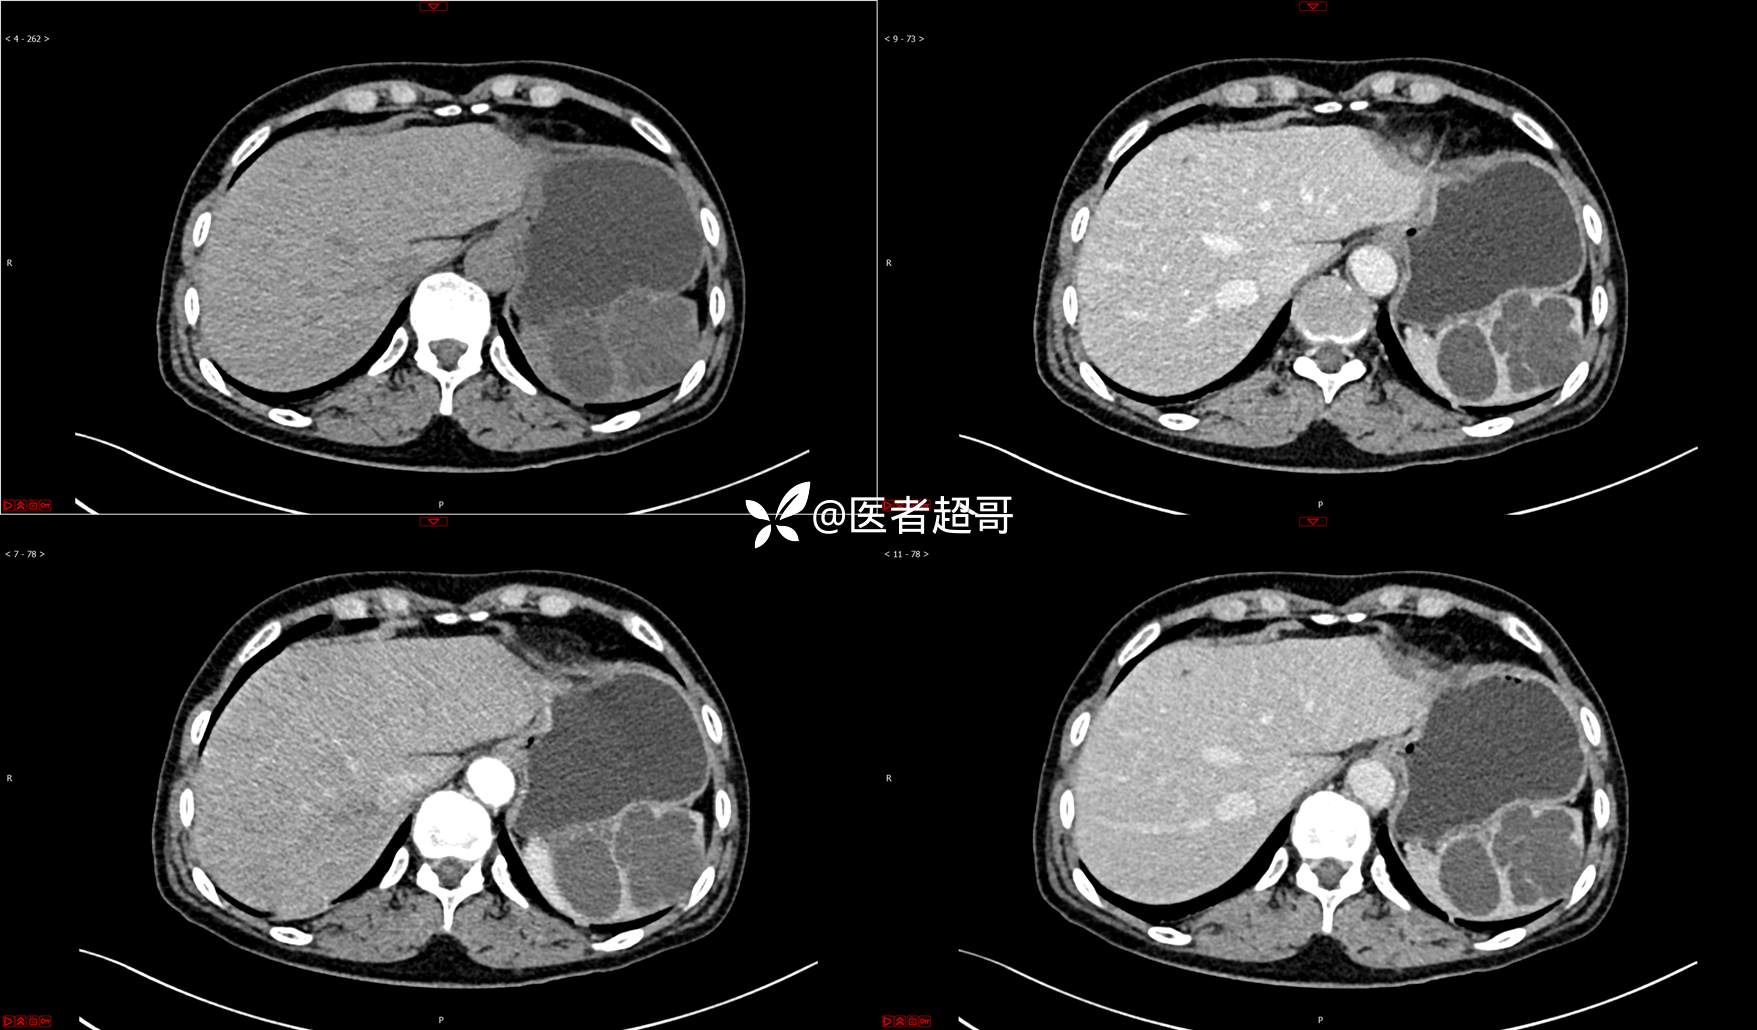

【影诊笔记739】脾脏囊性占位,查体偶发,请赏析,有病理!

主 诉:查体发现脾脏囊性占位4年。

现病史:患者4年前于人民医院查体时发现脾脏囊性占位。-04-20到我院复查,行上腹平扫+强化CT示:肝囊肿,脾脏囊实性占位,囊腺瘤?当时无明显症状,未行任何治疗。4个月前无明显原因及诱因开始偶尔出现左上腹疼痛,为隐痛,伴腰部放射痛,无腹胀、腹泻,无恶心、呕吐,无发热、畏寒、全身乏力,无胸痛、胸闷等其它不适。在外未行特殊治疗,今为求进一步诊治来我院就诊,行腹部彩超(肝、胆、胰、脾、肾)示:脾脏房囊性肿物。门诊以“脾占位性病变”收入院。发病以来,患者神志清楚,精神可,饮食可,睡眠欠佳,大小便正常,近期体重无明显变化。